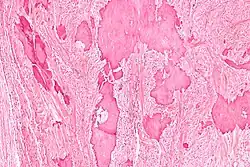

Low magnification micrograph of a calcified ovarian fibroma in the context of nevoid basal cell carcinoma syndrome. H&E stain. | |

On gross pathology, they are firm and white or tan. On microscopic examination, there are intersecting bundles of spindle cells producing collagen.

Diagnosis is usually made by ultrasonography showing a solid ovarian lesion, or, on some occasions, mixed tumors with solid and cystic components.[1] Computed tomography and magnetic resonance imaging can also be used to diagnose fibromas. In a series of 16 patients, 5 (28%) showed elevated levels of CA-125.[1] Histopathology demonstrates spindle-shaped fibroblastic cells and abundant collagen.[3]